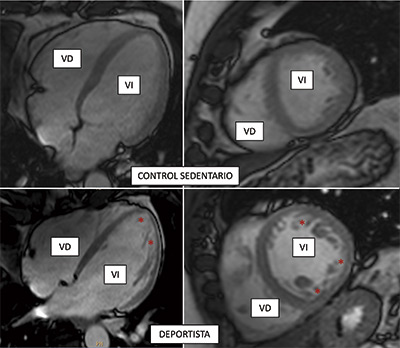

Vigorous exercise, spongy heart

Scientists at the CNIC and CIBERcv have used cardiac magnetic resonance technology to measure exercise-related hypertrabeculation in a general, non-athlete population. The results of the study have important practical implications because “misdiagnosis of noncompaction cardiomyopathy in people who exercise regularly (whether professional athletes or amateurs) can trigger medical recommendations to stop physical exercise unnecessarily,” explained CNIC General Director Valentín Fuster.

The authors conclude that cardiac magnetic resonance criteria for diagnosing noncompaction cardiomyopathy should not be interpreted in isolation. Instead, imaging results should be placed in the context of other clinical parameters, genetic tests, and the level of physical activity. This is important even in a population of non-athletes in order to avoid misdiagnosis of the disease. Misdiagnosis can result in the unnecessary cessation of exercise, with all its associated negative physical and psychological consequences.

The study, published in the Journal of American College of Cardiology (JACC), forms part of the PESA-CNIC-Santander study.